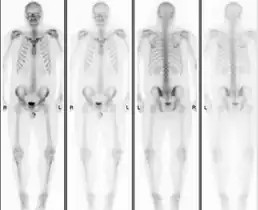

Normal bone scan in a person with osteopoikilosis